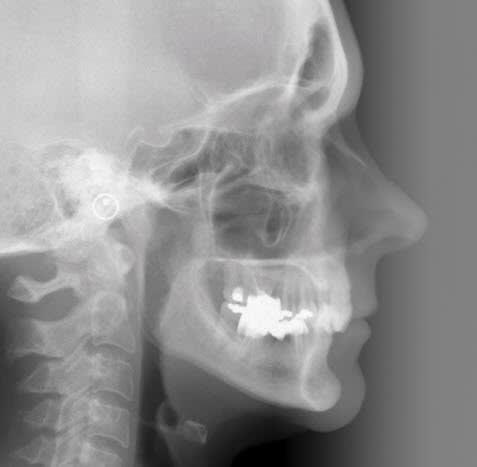

Si je les ingresse, je vais de facto augmenter leur support osseux, non ?

peut être radiologiquement, sur l'instant ...

mais histologiquement ? il faut une reconstruction du ligament pour perdurer

Le truc, c'est que les pbs paro sont généralisés et qu'en faisant l'ingression des dents, y a 9 chances sur 10 que tu n'obtiennes...que des poches paro plus profondes...

Comment espères-tu retrouver une attache alors que tu a perdu depuis belle lurette la zone cellulaire du cément sur 75% de la racine?

En admettant que tu arrives à ingresser, je crains que tu ne crées de la cratérisation...

Je pense qd même que sur la télé de profil final, la zone apicale des incisives est floue sur le plan osseux...

Et que de tte les façons le mur osseux vestibulaire est si fin que la pérénité est très très loin d être assurée mais ce n est que l avis de Pp :-)))))))))))))